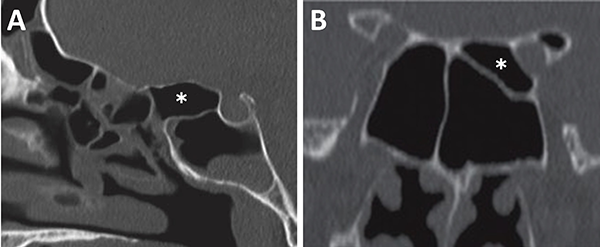

El grado neumatización del seno esfenoidal se puede clasificar en selar, pre selar y conchal (fig. 12).1,29,30,58 En el tipo conchal, el área bajo la silla turca es de hueso sólido sin neumatización. En el tipo preselar, el área neumatizada no penetra más allá del plano perpendicular de la pared selar. En el tipo selar, presente en el 86% de los individuos, la región neumatizada se extiende al cuerpo del esfenoides bajo la silla turca, pudiendo extenderse hacia posterior. Esta característica del seno es importante ya que ante la presencia de un tipo conchal es recomendable la utilización de neuronavegación.23,58

El grado de neumatización de etmoides posterior es variable. Se debe identificar si existe hiperneumatización del mismo, con extensión de celdillas a región superior y lateral se seno esfenoidal, variante que conocemos como celdas de Onodi. Su relevancia radica en mantener durante el intraoperatorio un adecuado corredor hacia la hipófisis, y evitar una “falsa vía”, con potencial lesión intracraneal (fig. 15).

Figura 15: Hiperneumatización de etmoides posterior. A) TC corte sagital; B) TC corte coronal, obsérvese la celdilla de Onodi (asterisco blanco).